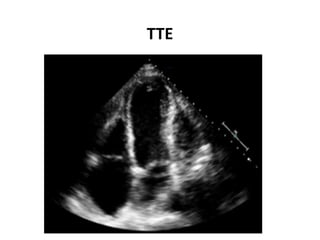

TTE

• Echo- Reaccumulation of pericardial fluid

posteriorly.

-apical hypokinesia, which is a different

distribution compared to that at the

time of STEMI.

• CXR- left sided pleural effusion